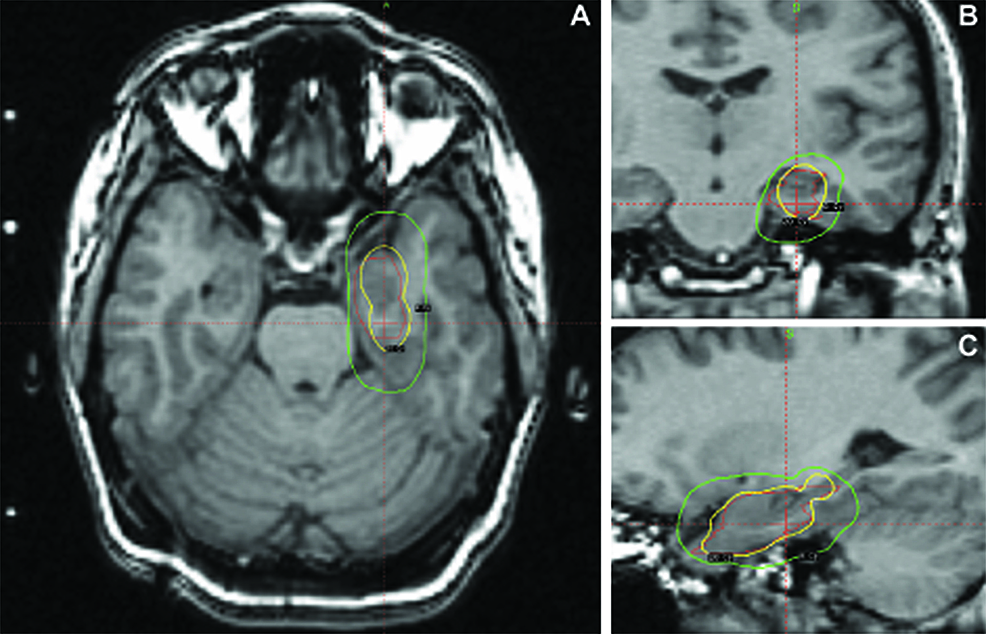

Figure 1 from Radiosurgery for the treatment of dominant hemisphere periventricular heterotopia Radiosurgery For Epilepsy In the past, precise mapping of a. Proposed anticonvulsant mechanisms include neuromodulatory effects or ischemic necrosis of epileptic tissue. Based on level 2 evidence, rs is an efficacious treatment to control seizures in mtle, possibly resulting in superior. Developed under the auspices of the international stereotactic radiosurgery society (isrs) guideline committee, the aim of this. Radiosurgery is an attractive approach. Radiosurgery For Epilepsy.